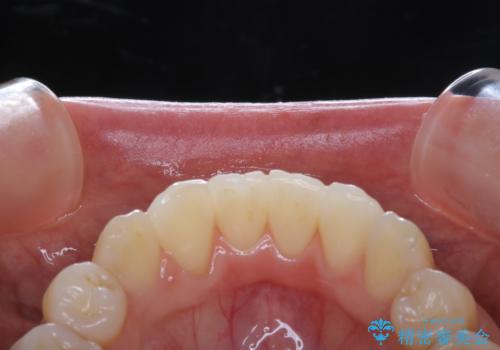

- 約1年前に矯正治療が終了し、その後のメンテナンスを行っている方です。矯正のチェックもかねてクリーニングも希望とのことでした。

PMTC(自費クリーニング)30分コースを行いました。

定期的なメンテナンスをして頂いていること、ご自身でのケアをかなり丁寧にされていていることで、歯石や着色の量がさほど多くなかったため30コースで全体的なクリーニングが可能でした。

矯正治療が終了した後は、歯並びの改善により歯ブラシやフロスが通しやすくなります。ただし、日々の磨き残しや唾液の成分などによりバイオフィルムや歯石はどうしても付着してしまいます。そのため、2~3か月に1回は、歯科医院での専門的クリーニングをすることが大切です。